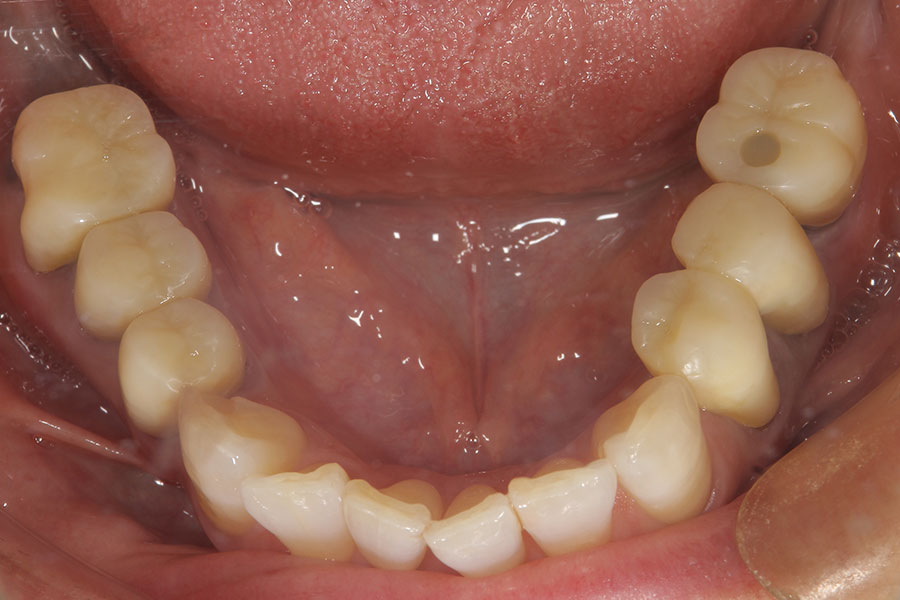

Before -下顎-

After -下顎-

| 施術内容 | 金属アレルギー予防を目的に、金属フリーの自費補綴へ変更。適合性・清掃性・審美性の向上が得られています。 |

|---|---|

| 治療期間 | 約4ヶ月 |

| 費用 | オールセラミックインレー 693,000円 |

| リスク・副作用 | 治療にともない、歯の破折や歯質の削合、場合によっては抜歯が必要となることがあります。また、金属や補綴物を除去する際に、完全に除去できない場合もあります。 |